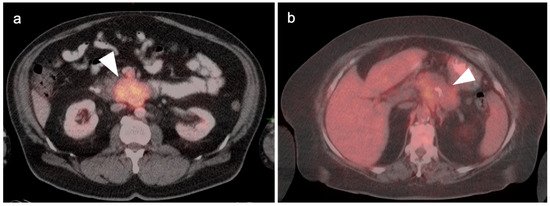

4. Hepatocellular Carcinoma

5. Cholangiocarcinoma